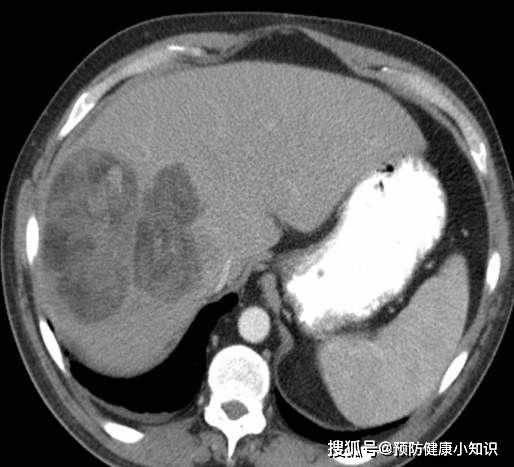

影像學檢查包括增强CT、超聲和磁共振,對於難以確診的病例,肝血管造影可能有助於診斷。如果影像學有特徵性的表現,且抱伴有甲胎蛋白升高,診斷可以明確。必要的時候,可以在超聲或CT引導下做肝活檢,以進一步明確診斷。